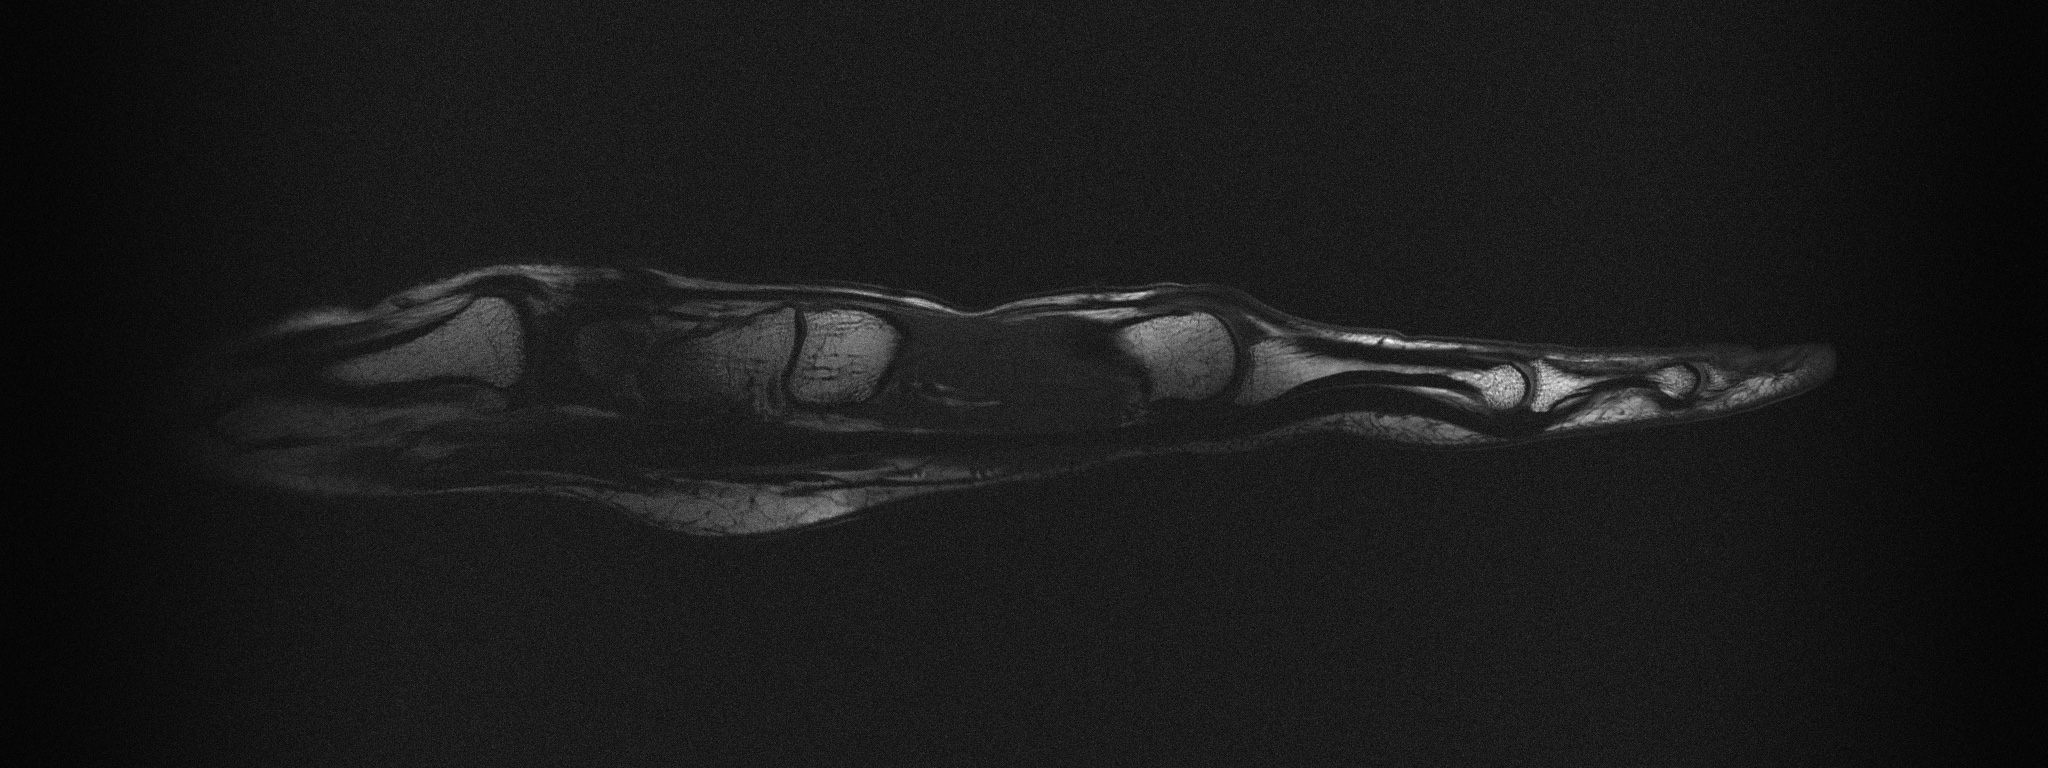

[Uncaptioned image]

Supplemental Figure 6: Sagittal T1 weighted image through the flexor tendon in the index finger while the hand is stretched out. Sequence parameters: TR=400ms, TE=15ms, excitation angle = 90, refocusing angle = 180, Turbo factor 2, 2024x512 Matrix, 303.6x76.8mm FOV, 2mm slice thickness, 150x150 μ𝜇\mum resolution, total scan time = 1min 42s.